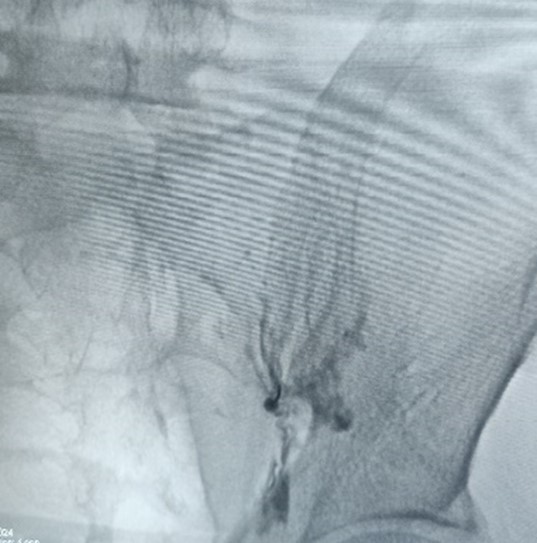

This MIPSI intervention is targeted at injecting a very low dose of steroid into the joint space under the guidance of Fluoroscope machine. This brings about reduction in the inflammation of the joint reducing the pain and stiffness of the joint.

This MIPSI intervention is targeted at injecting a small volume of Platelet rich plasma into the joint space under the guidance of Fluoroscope machine. This not only brings about reduction in the inflammation of the joint but also initiates the healing process inside the degenerated joints, reducing the pain and stiffness of the joint.

In cases of severely degenerated Sacro-iliac joints, only joint injections are not helpful. In these cases, Lateral branches of Sacral nerves which specifically supply the SI joints are targeted with the help of radiofrequency ablator, which bring about Wallerian degeneration in these nerves, thus blocking the pain signals and bringing about pain relief.